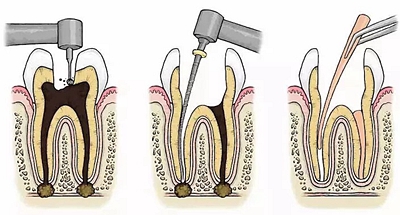

根管治療步驟

1.開髓:即將患牙打開,暴露髓腔。

2.根管預(yù)備:通過(guò)不同器械在牙根里面切削清理擴(kuò)大根管。

3.沖洗消毒:對(duì)患牙充分沖洗、消毒滅菌,然后封消毒液一周。

4.根管充填:一般放置人工無(wú)菌材料,封閉腔體。

5.對(duì)牙冠方向的缺損進(jìn)行填充修復(fù)。一般整個(gè)治療過(guò)程需要就診兩到三次,根據(jù)患者情況而定。